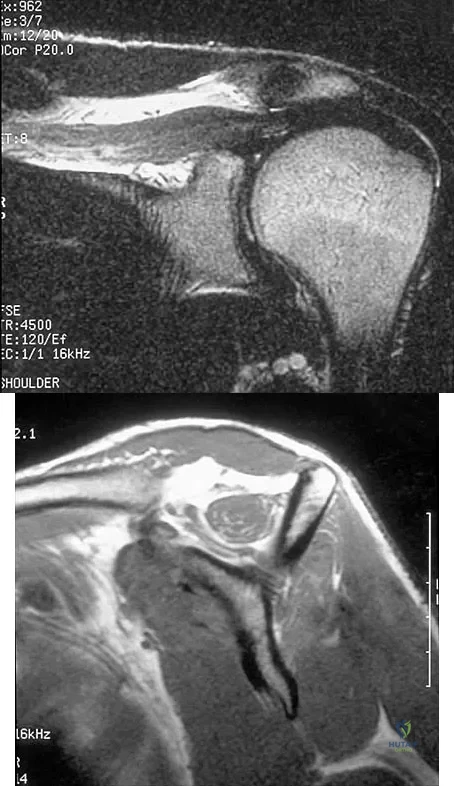

Question 96

Figures 36a and 36b show the MRI scans of a patient who has shoulder weakness. What is the most likely diagnosis?

Explanation